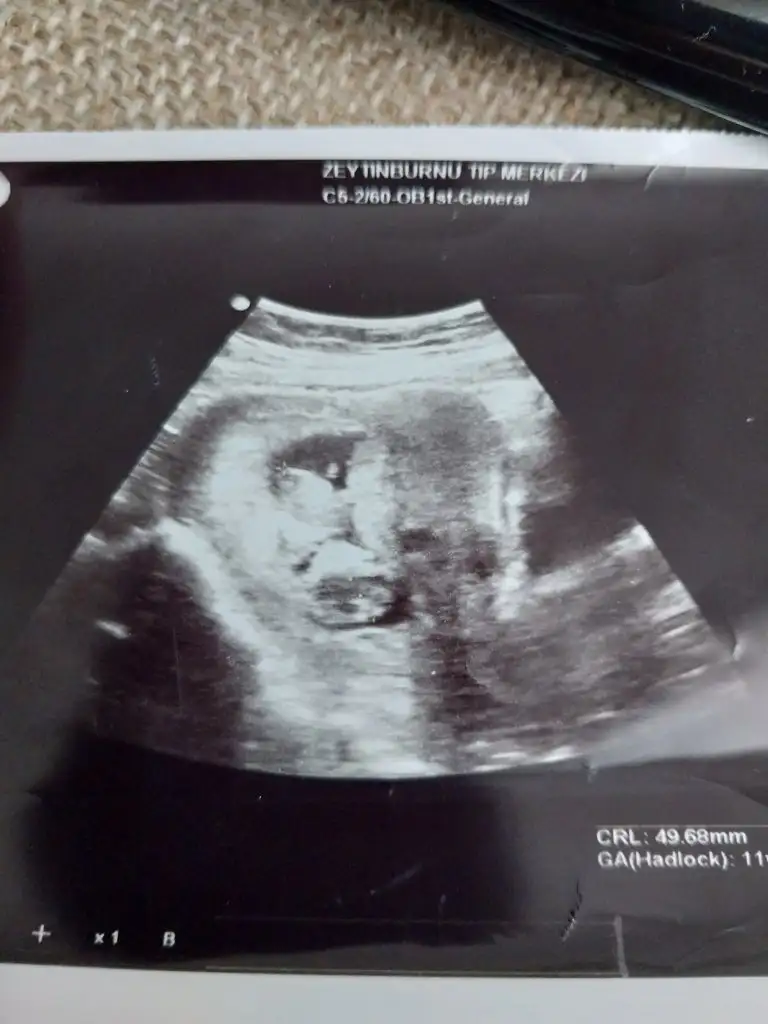

Merhaba lar hanımlar ilk 2 resim 11 haftalikken diğer resimlerde 15 haftalikken banada tahminde bulunurmusunuz

12 haftalık bende çok kerak ediyorum yorumlar mısınızz🥰

Sırayla 8-12-14 hafta hepsi karından yorumlarsanız sevinirim

12 haftalıkken erkege benziyor denildi 14 hafta kıza benziyor denildi 15 haftalık oldum hala bilmiyorum bebisimin cinsiyetini dahada doktora gitmeme 3 hafta var meraktan çatlamak üzereyim 😅